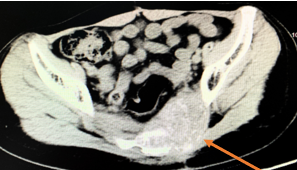

2018年9月20日CT:

0.44*0.4

7.64*4.32

2019年1月28日CT:

0.64*0.71

7.71*4.32

骨转移灶实性成份增多,疼痛明显加重。